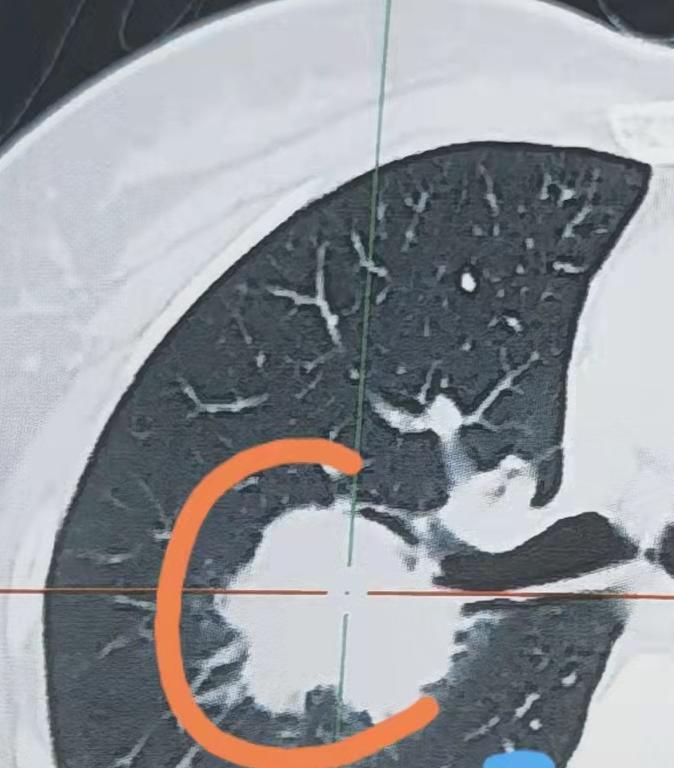

戒烟不到2年,为什么还是得了肺癌?前阵子,一位有着20多年烟龄的老朋友,一脸困惑地找到我。他戒烟还没满2年,就被查出了肺癌,见面第一句话就带着委屈和不解:“乔主任,我是真的下决心戒烟了,怎么还是得了肺癌?难道戒烟反倒害了我?” 其实不光是他,很多朋友都有过类似的疑问,但大家首先要明确一点:吸烟和肺癌的关系,在医学上早就有了定论,两者联系非常紧密。长期大量吸烟,对肺部的伤害是实打实的,没有任何疑问。 很多人可能觉得,只要一戒烟,身体就能马上恢复正常,之前吸烟的伤害就能一笔勾销,其实不是这样的。就算你成功戒烟了,之前十几年、几十年吸烟给身体带来的潜在伤害,短时间内根本消不掉。 现在很多研究都能证明,吸烟的人得肺癌的风险,比不吸烟的人高得多,但这并不代表,只要吸烟就一定会得肺癌。简单说就是,吸烟会大大增加患肺癌的几率,而不是必然会得。 而且这个患病风险,和你吸烟的量、吸烟的年限直接相关。每天抽得越多,烟龄越长,肺部受到的伤害就越严重,得肺癌的可能性也就越大。 就说这位老朋友,20多年来,每天吸烟量都不小,这么多年的坏习惯,早就把肺部细胞伤得很严重了。他后来虽然戒烟成功了,但之前二十多年积累的伤害,已经在身体里埋下了隐患,所以就算戒了烟,也依然有可能患上肺癌。 除此之外,大家也能发现,现在很多不吸烟的人,也会查出肺癌。这就说明,肺癌的发病原因并不是单一的,除了吸烟之外,遗传因素、生活环境、日常作息习惯等,都有可能诱发肺癌。 所以,戒烟只能大大降低患肺癌的风险,并不能完全排除这种可能性。[作揖][玫瑰]